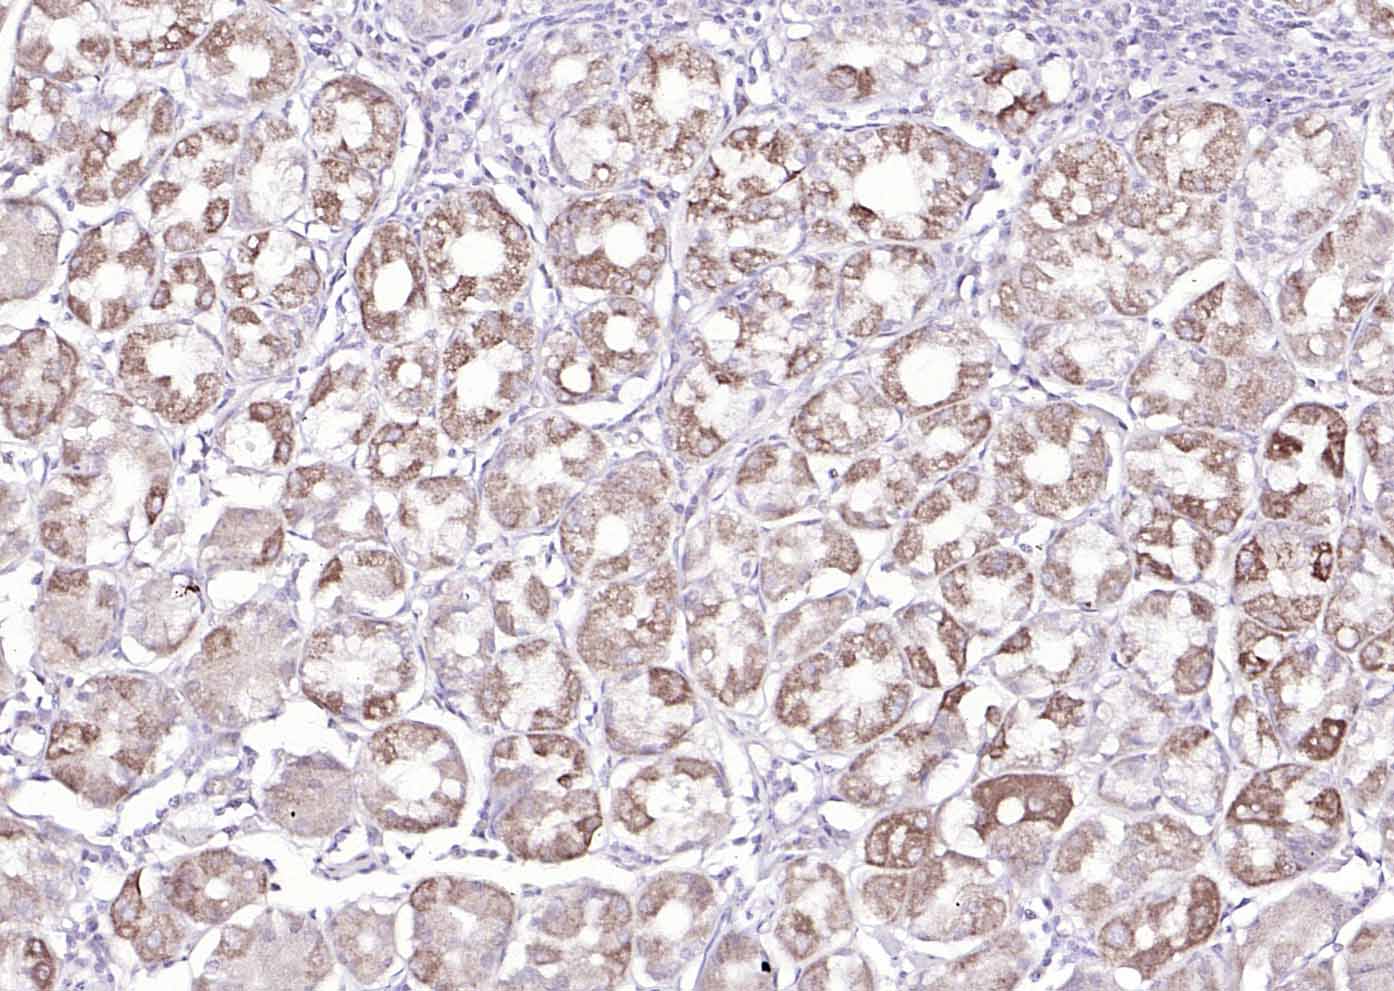

Paraformaldehyde-fixed, paraffin embedded (human pancreatic carcinoma); Antigen retrieval by boiling in sodium citrate buffer (pH6.0) for 15min; Block endogenous peroxidase by 3% hydrogen peroxide for 20 minutes; Blocking buffer (normal goat serum) at 37°C for 30min; Antibody incubation with (MUC5AC) Polyclonal Antibody, Unconjugated (bs-7166R) at 1:200 overnight at 4°C, followed by operating according to SP Kit(Rabbit) (sp-0023) instructionsand DAB staining.